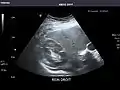

Left kidney